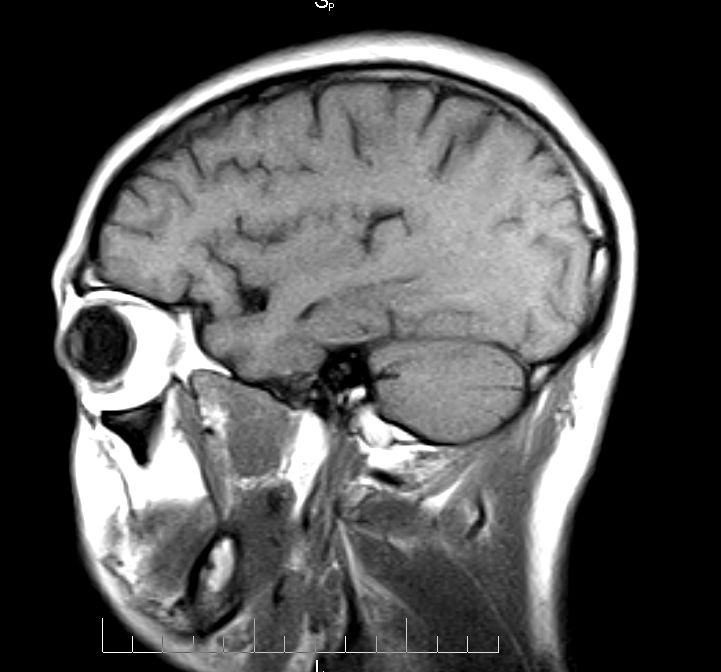

标题: MRI2379:30岁,男,癫痫10年,请各位看一下;CT示:左颞叶钙 [打印本页]

标题: MRI2379:30岁,男,癫痫10年,请各位看一下;CT示:左颞叶钙

左颞叶区见不规则点状混杂信号影

支持2楼 左颞叶区见不规则点状混杂信号影,考虑动静脉畸形。

考虑左侧颞叶脑血管畸形(avm)。----t1低等高混杂信号,t2等高信号周边较多流空血管影[冠状位明显],mra左侧大脑中动脉受压,远侧聚集.